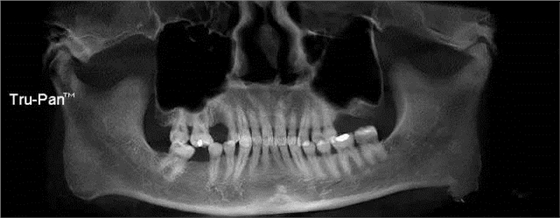

第七圖:斜坡型上頜竇底,圖中右側(cè)上頜竇就是次類型,進(jìn)行上頜竇內(nèi)提升較為困難。可改外提升手術(shù)。

第八圖:有間隔的上頜竇。上頜竇底中間有骨間隔,通常增大了上頜竇外提升開窗的困難。 北一種植老師主張開兩個小窗,有些醫(yī)生也可以開W型窗,來降低難度。